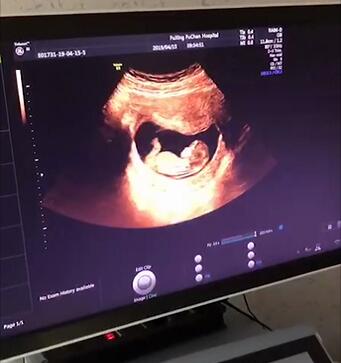

需要做大排畸,通过四维彩超,检查胎儿器官的发育是否正常。